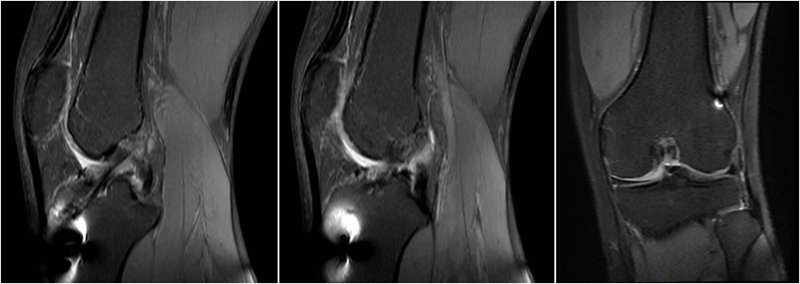

术前MRI

术后MRI

MRI检查评估ACL-R术后——韧带连续性信号好、方向好、愈合快,没有Cyclops综合征。